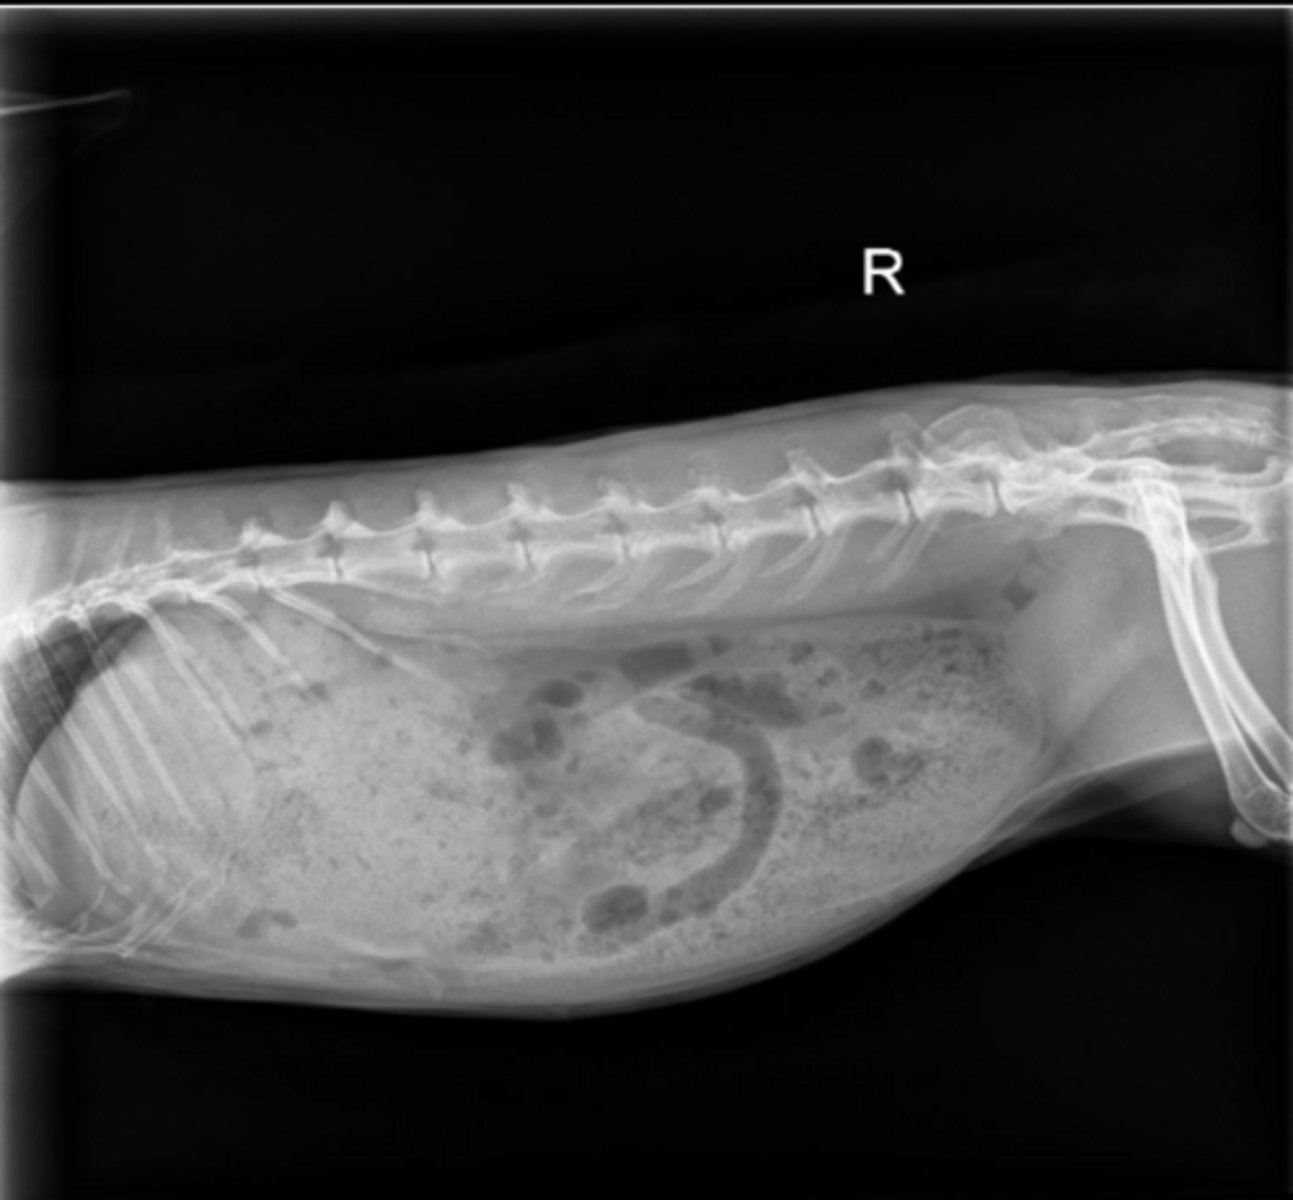

Normal

Is this a normal OR abnormal rabbit?

The caudal border of the stomach should not pass the caudal border of L2

How do you determine if the stomach is normal size on rabbit x-rays?

There is lots of gas in the cecum and the stomach is getting large.

Give IV fluids, syringe feed, lidocaine CRI

What do you want to do for this rabbit, who has recently been spayed?

Hyperglycemia associated with GI obstruction. This patient is also hypothermic.

Give thermosupport, surgery, may sedate and pass orogastric tube to relieve pressure in stomach

This rabbit has a temperature of 98.1 F. There is a firm, cranial abdominal mass. The bloodwork is normal apart from hyperglycemia of 641. What is likely happening here and how do you treat?